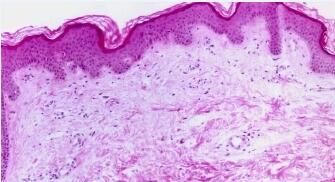

胆碱能性荨麻疹目前属于人们常讲的风疹。当精神过度紧张的食物或饮料,或在运动之后,体温可逐渐减退,兴奋胆碱能性神经并释放出现很多乙酰胆碱,我们将过敏而引发的症状可称为胆碱能性荨麻疹。那么下面就请京城专家为您具体的讲解一下吧。希望能给大家带来一定的帮助!

胆碱能性荨麻疹的症状如下:

一、不会产生皮疹,但明显感到有针刺、疼痛感。

二、一般多发于青年阶段,一般在遇热、情绪过于激动和运动之后才会产生。当停止运动或平静后,症状即可去除,严重的话,症状可弯曲消失可能要经过数月不等。

三、常在躯干和近端皮肤才可产生红色的2 毫米左右的风团,这种风团速来不留痕迹。严重者可时常伴有消化肠道症状,如腹痛、干燥等。